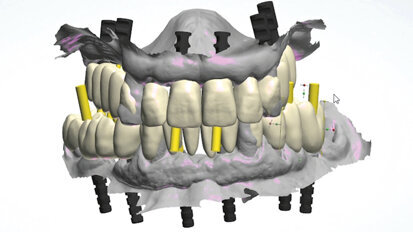

Plně digitální Pro Arch protokol

Pro Arch od společnosti Straumann je koncept, který zahrnuje různá léčebná řešení pro zcela bezzubého pacienta. Cílem je poskytnout ...